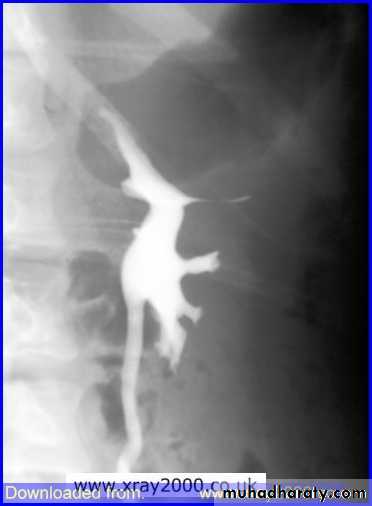

IVU :-* Nephrogram shows filling defect .

*Displacement , elongation & stretching of PCS which depend on size and site of the cyst .